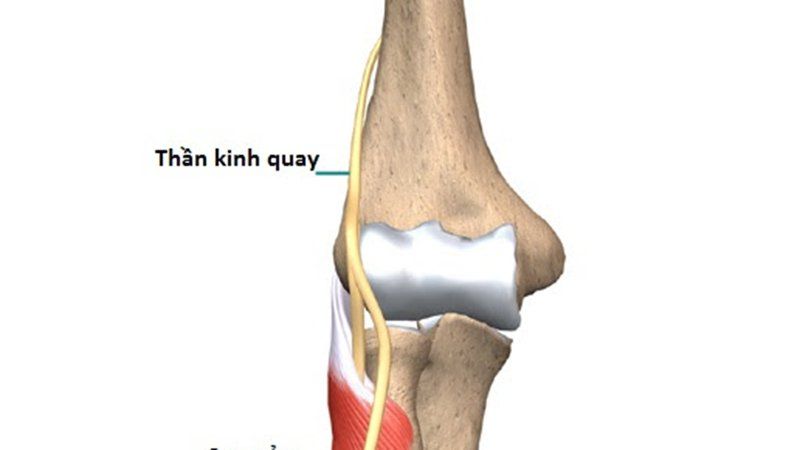

Dây thần kinh hông là dây hỗn hợp lớn nhất của cơ thể. Mọi áp lực gây ra bởi tư thế ngồi bắt chéo chân đều có thể khiến dây thần kinh hông bị tê, thói quen này kéo dài lâu dần có thể dẫn đến tổn thương.